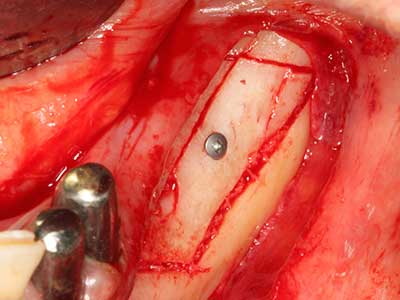

Wie sich in der Vergangenheit gezeigt hat stellt prinzipiell jeder knochenchirurgische Eingriff eine mögliche Indikation für die Piezochirurgie dar. So lässt sich die Präparation des mobilen Segmentes bei der Distraktionsosteogenese (Abb. 23-25) und der Sandwichosteotomie mit speziellen Ansätzen bewerkstelligen, ohne die für den Erfolg beider Techniken essenzielle Blutversorgung des krestalen Anteils zu gefährden (Gonzalez-Garcia, Diniz-Freitas et al. 2008).